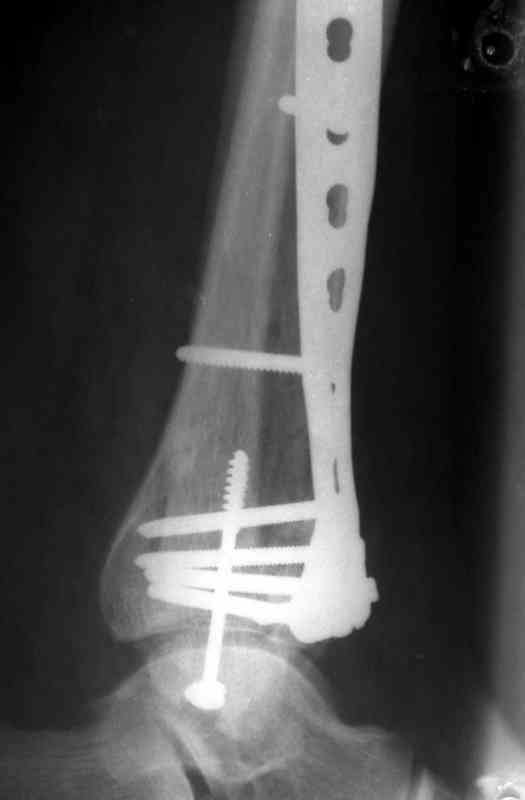

Кстати, при переломах переднего края по классификации АО В-3 при переломах пилона пластина укладывается по передней поверхности. Она достаточно тонкая и эластичная, не надо этого бояться. Посылаю три снимка.